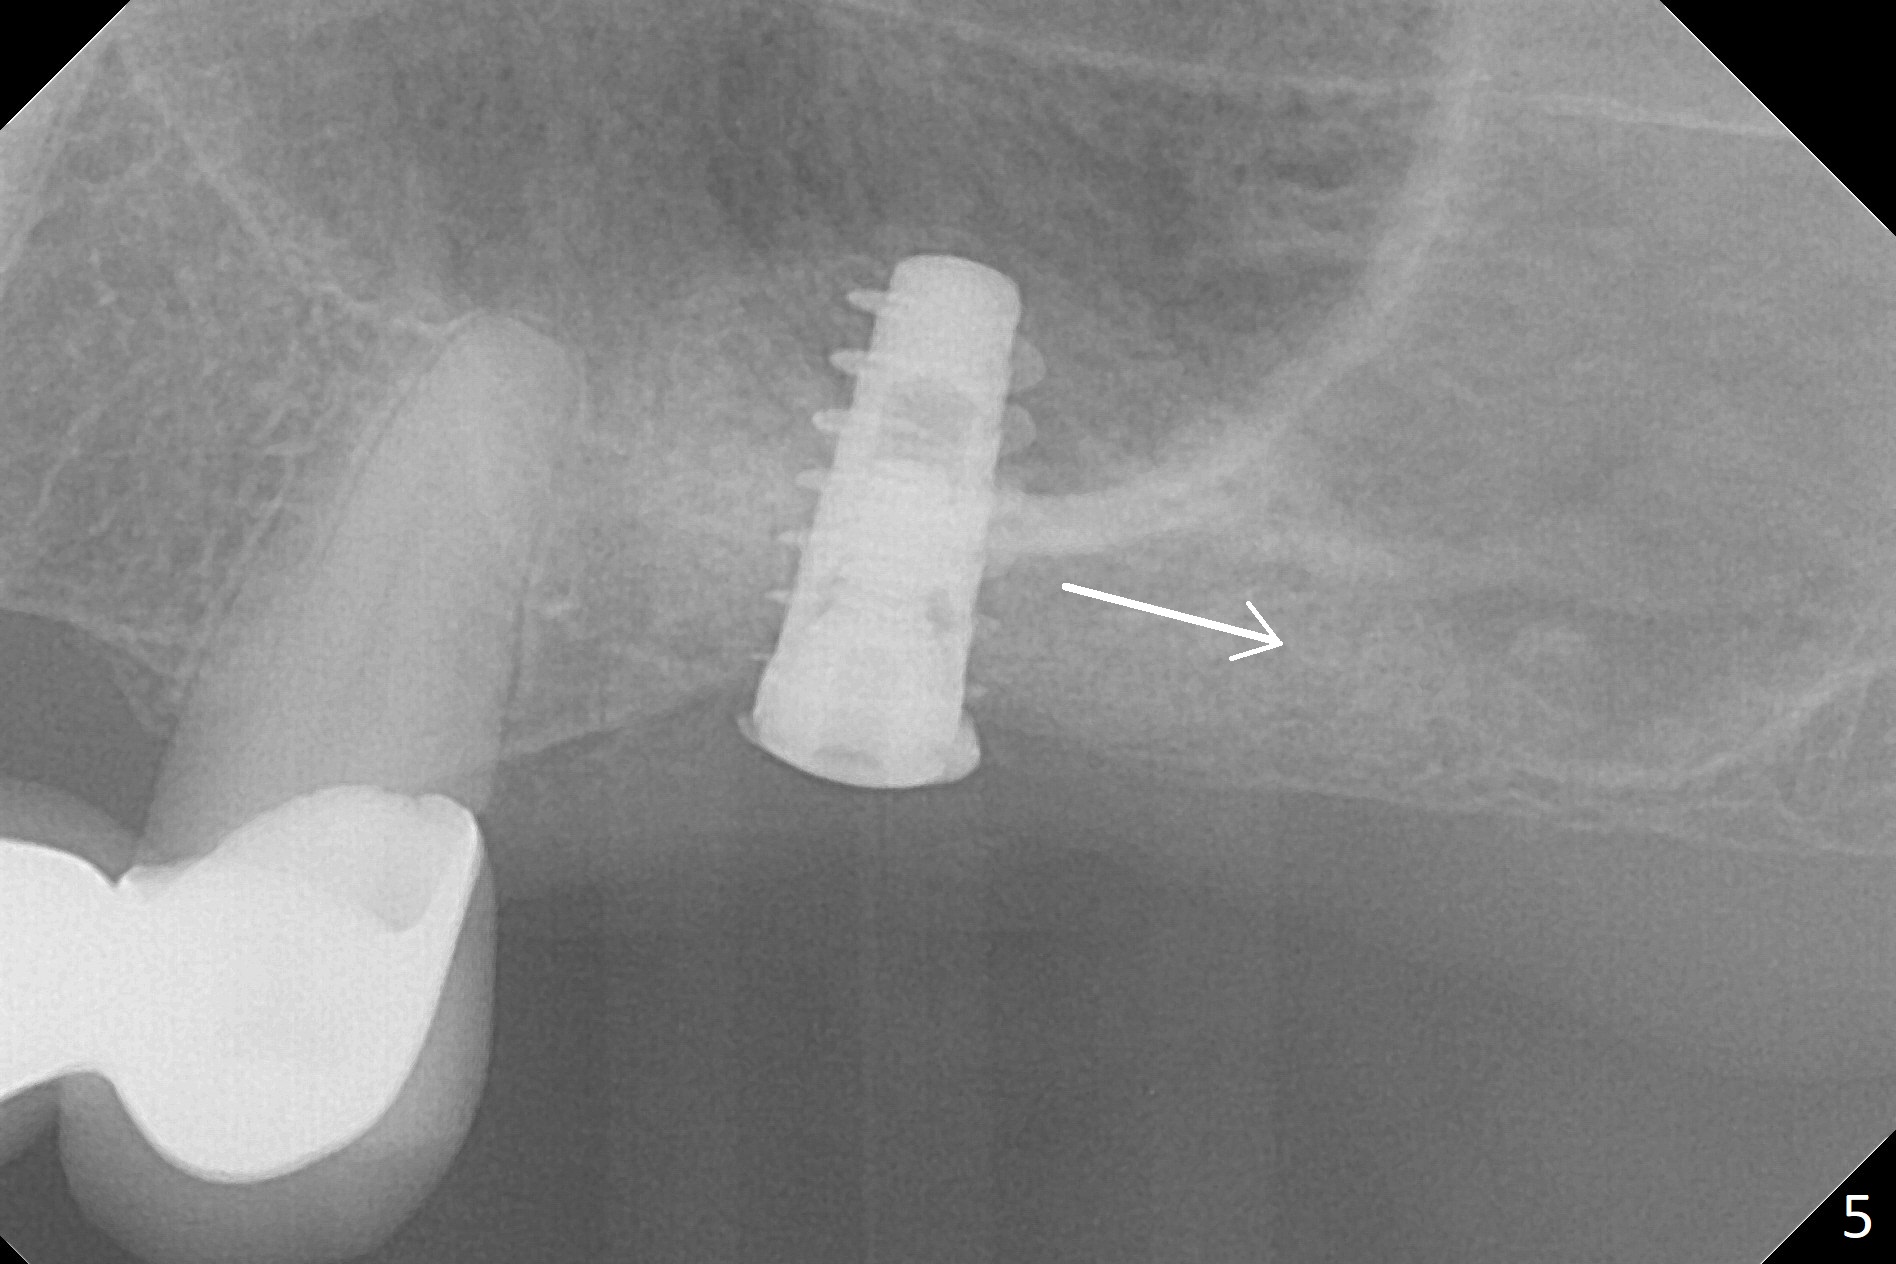

The bone graft appears to move distal 1 month 20 days postop (Fig.5 arrow), while the implant seems to be extruded with implant exposure. The patient feels pain when the healing screw is being removed or tightened. The distal migration of the bone graft may lay foundation for future implant placement at #15. Bone density around the implant remains the same (Fig.6), while the wound reduces nearly 3.5 months postop (Fig.7). The healing screw cannot be turned without causing pain. Can the implant at #14 be retorqued to be seated deeper 3-4 months later?